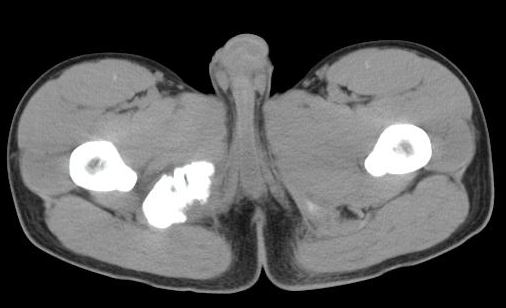

男性,15岁,半年前曾有做运动摔伤史,伤后左肢麻木,一天后恢复,两个月后因右臀部隐痛照片示右坐骨下骨性密度影,现复查见骨性影无明显改变。求助诊断!

坐骨粗大,有瘤骨,基地部有囊状骨缺损。不应为外伤史迷惑,应考虑外生软骨瘤病或骨膜硬纤维瘤。请勿见笑。

坐骨撕脱性骨折伴骨化性肌炎

如果是撕脱骨折,应该有疼痛,而病史是伤后左肢麻木,一天后恢复,两个月后因右臀部隐痛才就诊,病变在肌肉区,故考虑骨化性肌炎

支持坐骨撕脱性骨折合并血肿机化、骨化。

坐骨陈旧性撕脱性粉碎性骨折伴骨痂形成.